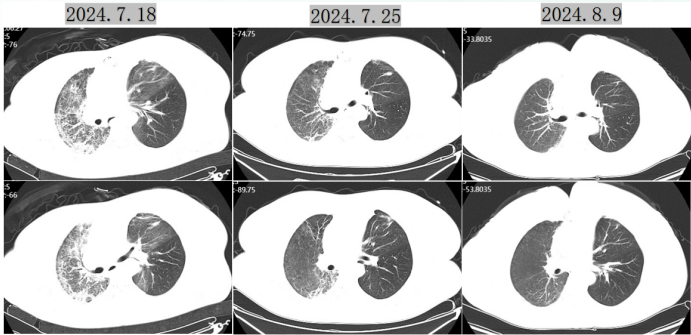

影像学:7月6日胸部CT示双肺多发斑片状磨玻璃影,上肺为著(图3)

图片

3  患者入院时胸部CT

明确病原学:BALF mNGS检出耶氏肺孢子菌(序列数1349)。

7月21日后患者呼吸衰竭改善,8月9日复查胸部CT示磨玻璃影吸收(图4)

4  患者胸部CT动态演变